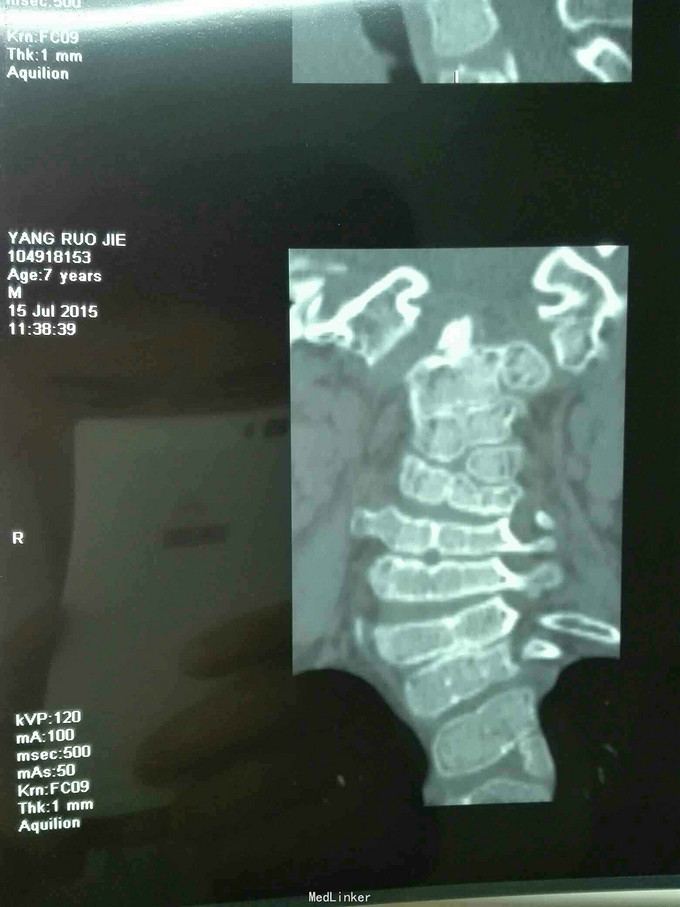

先天脊柱畸形

先天脊柱畸形8年。